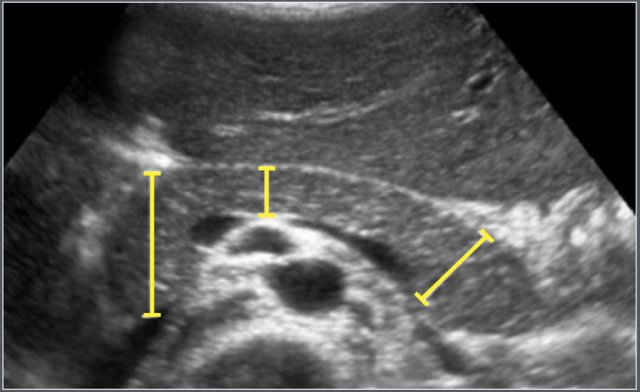

Two hundred and seventy-three patients (differentiation in sex not mentioned) were included in this retrospective ultrasonography study.

The maximum anteroposterior (AP) diameters of the head, body and tail of the pancreas were measured on transverse/oblique images.